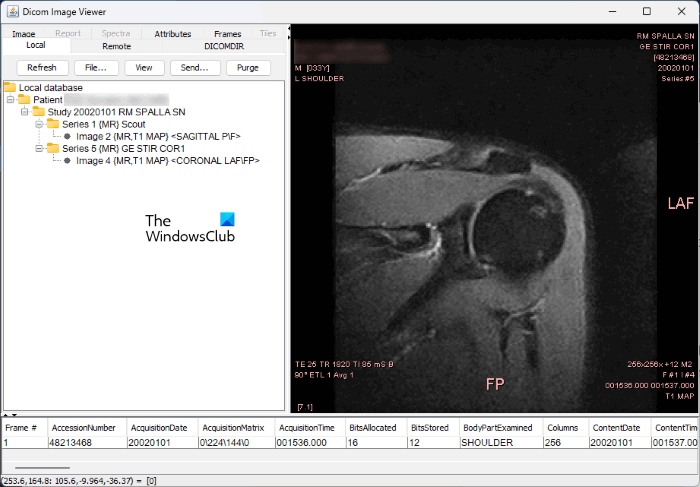

5] Dicom Image Viewer

Dicom Image Viewer is a simple DICOM Viewer software. Unlike the other DICOM Viewer software on this list, this software does not have any additional features. You can use it to open the DICOM files only. Dicom Image Viewer is portable. Hence, you need not install it on your computer.

It is available as a JAR file. Hence, you need to install JAVA on your Windows computer to open the JAR file. To open a DICOM file, click on the File button and select the file from your computer. It automatically loads the patient’s database after uploading the DICOM file. Some image options are available under the Image tab. To view the attributes, click on the Attributes tab. To change the brightness level of the DICOM image, press and hold the left mouse click and move your mouse over the image.

You can download Dicom Image Viewer from softpedia.com.